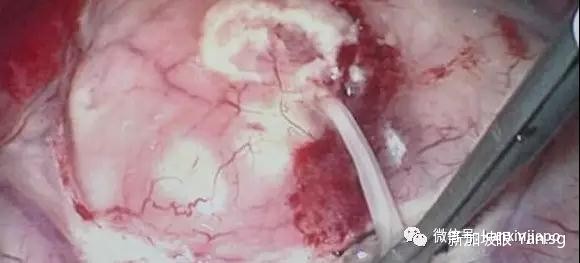

重者,蟲卵或幼蟲會進入血液,隨後進入大腦,並在大腦停留、繁殖。抽搐、昏厥、癫痫等症狀也是常有發生。

(腦中取出的曼式裂頭蚴蟲)